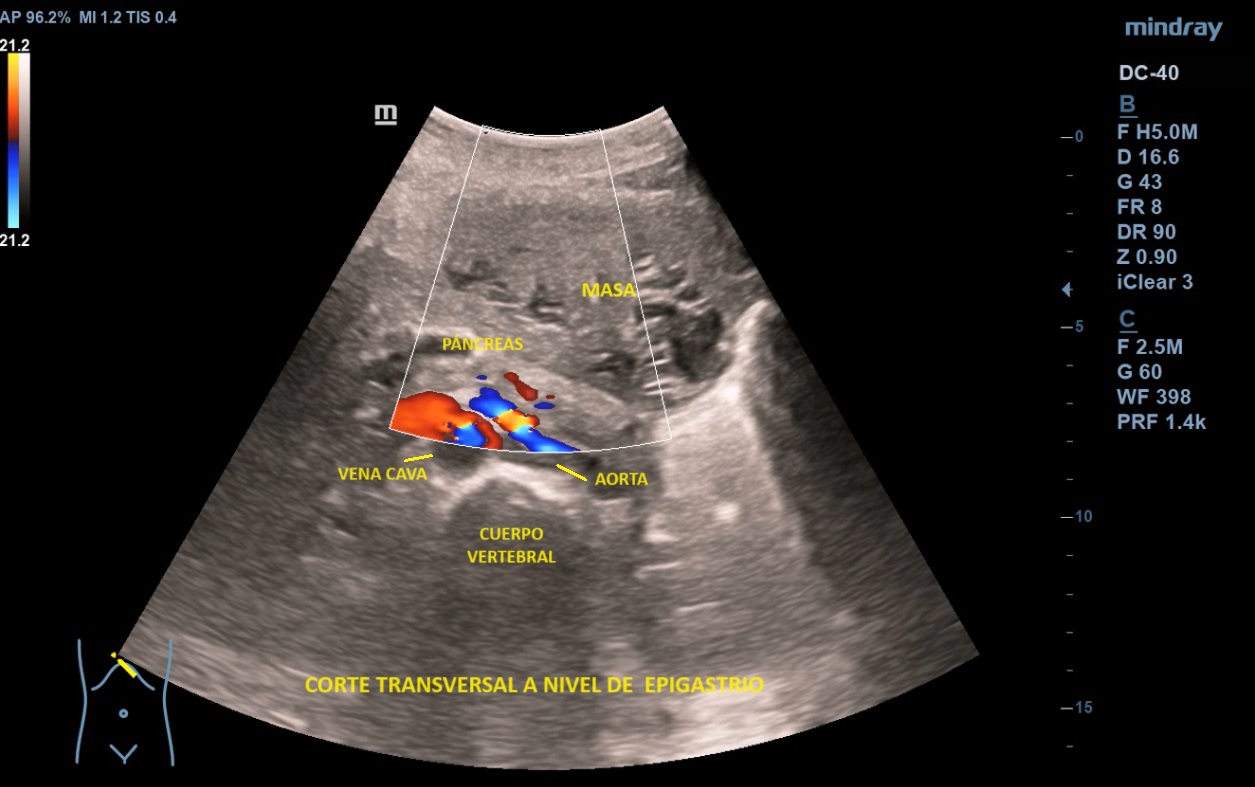

Ecografía abdominal clínica: Masa heterogénea que ocupa todo el abdomen, de aspecto sólido, vascularizada con zonas hipoecoicas-anecoicas en su interior. Riñones con eco-estructura sin alteraciones, hígado sin LOES. Vejiga sin engrosamiento de paredes, útero parcialmente visible. Anejos y retroperitoneo no valorables. No líquido libre.

Se deriva a urgencias donde realizan ecografía transvaginal confirmando presencia de masa que parece depender de anejo derecho. Solicitan TAC toraco-abdomino-pélvico objetivando «masa abdominal gigante de dudosa dependencia ovárica, no pudiendo descartar liposarcoma abdominal». Citan a la paciente para RM donde se demuestra contacto pero no dependencia de masa abdominal, probable liposarcoma, de anejo derecho, de características normales. Analítica con marcadores tumorales sin alteraciones.

e describen como masas bien delimitadas redondeadas hipoecoicas con sombra acústica, aunque también pueden tener áreas isoecoicas e hiperecoicas. Pueden presentar necrosis central (áreas anecoicas) o calcificaciones, sin implicar malignización. El Doppler-color suele mostrar una distribución irregular de los vasos. El diagnóstico definitivo es el anatomo-patológico.